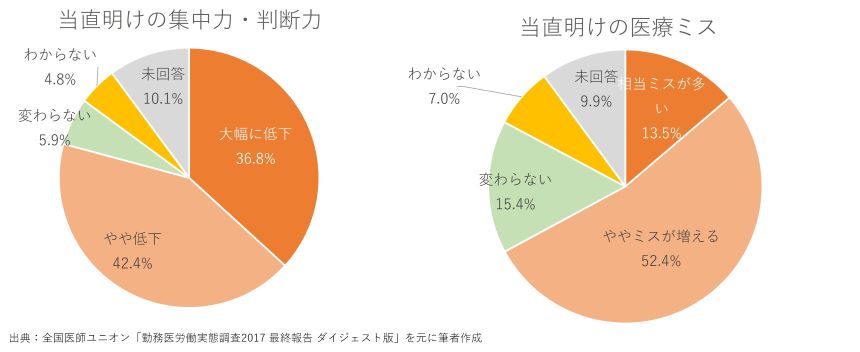

疲労による注意力不足については、8割の医師が当直勤務後の通常勤務で集中力・判断力が低下していることを認めています。前述の通り、当直明けの医師の約8割が通常勤務についており、当直明けの通常勤務では電子カルテの入力ミスなど単純なものも含めて、診療上のミスが通常時より増えると回答した医師は6割強でした。

出典:全国医師ユニオン「勤務医労働実態調査 2017 最終報告 全文」ドクターズ・ユニオン ニュース 第23号 P.22

全国医師ユニオン「勤務医労働実態調査2017 最終報告 ダイジェスト版」 p.5